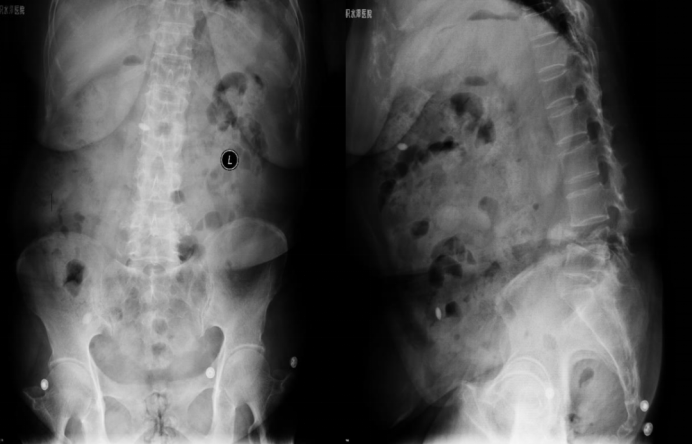

· Surgical Treatment: Spinal fusion surgery from L2 to S1, including:

o Lumbar laminectomy (decompression)

o Discectomy

o Pedicle screw internal fixation (utilizing a 4.75 system: 8 screws, 2 rods)

o Interbody cage placement

o Anterior mesh cage placement

o Bone grafting fusion (using a titanium mesh cage)

Preoperative Imaging

6-month postoperative imaging

6-Month Postoperative Follow-up:

6-Month Postoperative Follow-up: The position of the internal fixation hardware remains unchanged compared to the immediate postoperative status. Hyperextension angle: 17.5°; Hyperflexion angle: 15.1°; Intervertebral angular difference: 2.4°; Intervertebral translation distance: 0 mm. The implant shows no signs of deformation, displacement, loosening, or fracture. CT scan indicates fusion. Local reaction is Grade 0. Both the patient's lumbar spine functional score and quality of life score have improved compared to preoperative levels.